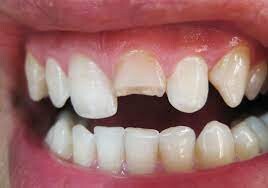

Cracks

A cracked tooth is a welcome mat to tooth and gum problems and it can affect more than just your mouth.

Whether from chewing ice or hard candy, sport injuries, accidents or teeth grinding, or because the tooth was weak to begin with, cracks can happen at any age. When a crack occurs, you may notice pain when chewing or when eating something very hot or very cold. Pain may be sporadic, or you may not feel any at all.

Cracks in teeth can irritate the gums. Depending on the severity of the crack, there are different courses of treatment. If the crack is shallow, topping it with a protective crown might save the tooth. If the crack extends to the root, then a root canal is needed before the crown. This might save the tooth. However, if the crack goes below the gum line, then it’s likely untreatable and the tooth must be extracted. Should this happen, you will have options for replacing the tooth — either partial denture, bridge or implant.

Complications of a crack include easier entry of bacteria to the pulp of the tooth and under the gum, causing decay and even infection. Additionally, a cracked tooth that is left alone may eventually break, leading to the need for an extraction. Damaged teeth become missing teeth.